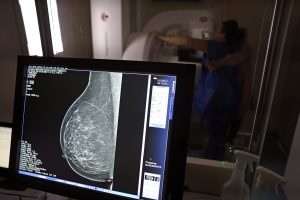

Dados do Panorama do Câncer de Mama revelam que o Brasil possui menos de 24% de cobertura mamográfica, bem abaixo dos 70% recomendados pela Organização Mundial da Saúde (OMS). O estudo também aponta disparidades raciais significativas: 44% das mulheres pretas e pardas recebem diagnóstico tardio, contra 36% das brancas. Especialistas alertam para a necessidade de melhorar o acesso e a conscientização sobre a importância do rastreamento.

Segundo estudos, essas mudanças no estilo de vida podem diminuir em até 30% as chances de desenvolver a doença. Já a prevenção secundária, igualmente crucial, envolve o rastreamento sistemático por meio de mamografias anuais a partir dos 40 anos para a população em geral, com início mais precoce para mulheres que apresentem histórico familiar significativo ou mutações genéticas conhecidas que aumentem o risco. Muitas mulheres enfrentam dificuldades logísticas, como a distância dos serviços de saúde e horários incompatíveis com suas rotinas, o que contribui para baixa adesão, além da falta de conscientização sobre a importância da mamografia.

Ao identificar uma lesão suspeita na mamografia, o próximo passo é realizar uma biópsia para confirmação histológica. Uma vez diagnosticado, o tratamento pode incluir cirurgia (desde abordagens conservadoras até mastectomia), hormonioterapia, quimioterapia, radioterapia ou imunoterapia, dependendo do tipo e estágio do tumor.